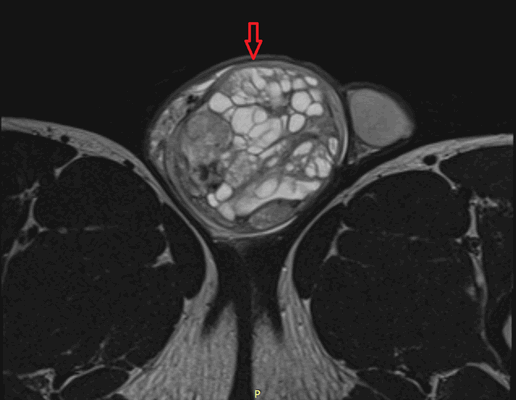

Рисунок 3. - тератома яичника а -УЗИ, б — МРТ.

- УЗИ. «Ультразвук» нужен для того, чтобы выявить первичный очаг как гонадной (в половых органах), так и внегонадной герминогенной опухоли. Его также проводят в ходе терапии, чтобы оценить ее эффективность.

- КТ (расшифровка: компьютерная томография), МРТ (расшифровка: магнитно-резонансная томография), ПЭТ-КТ (расшифровка: позитронно-эмиссионная томография, совмещенная с КТ). Эти обследования необходимы, чтобы рассмотреть структуры организма послойно и визуализировать опухоль. Они показывают, как сильно распространен патологический опухолевый процесс на находящиеся рядом ткани и органы, есть ли поражение костей. КТ - это самый чувствительный метод для обнаружения метастазов в легких. Проведение МРТ и КТ головного мозга необходимо, чтобы обнаружить и визуализировать герминогенные новообразования эпифиза.